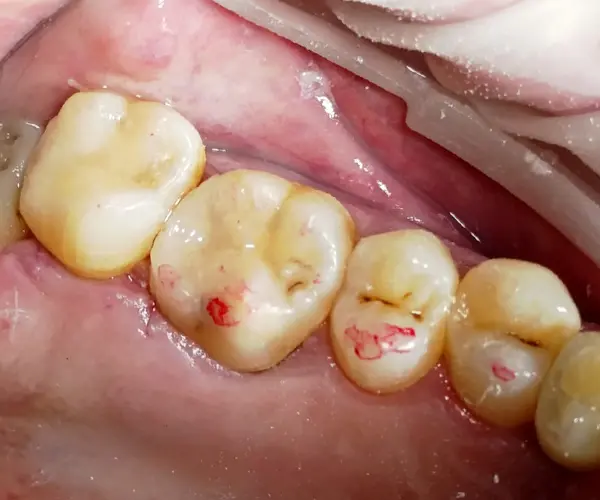

После этапа препарирования доктор принял решение работать в комбинированной технике с использованием материалов линейки B&E.

- B&E Flow: использовался как адаптивный слой и для моделировки дистальной стенки.

Важный нюанс: этот текучий композит обладает уникальной стабильной консистенцией. Он отлично контролируется, что позволяет формировать апроксимальные стенки с высокой точностью. - Xs-Fil (пакуемый композит): стал основой реставрации. Для воссоздания естественного цвета и объема применялась линейная техника с оттенками AO3 и A2.